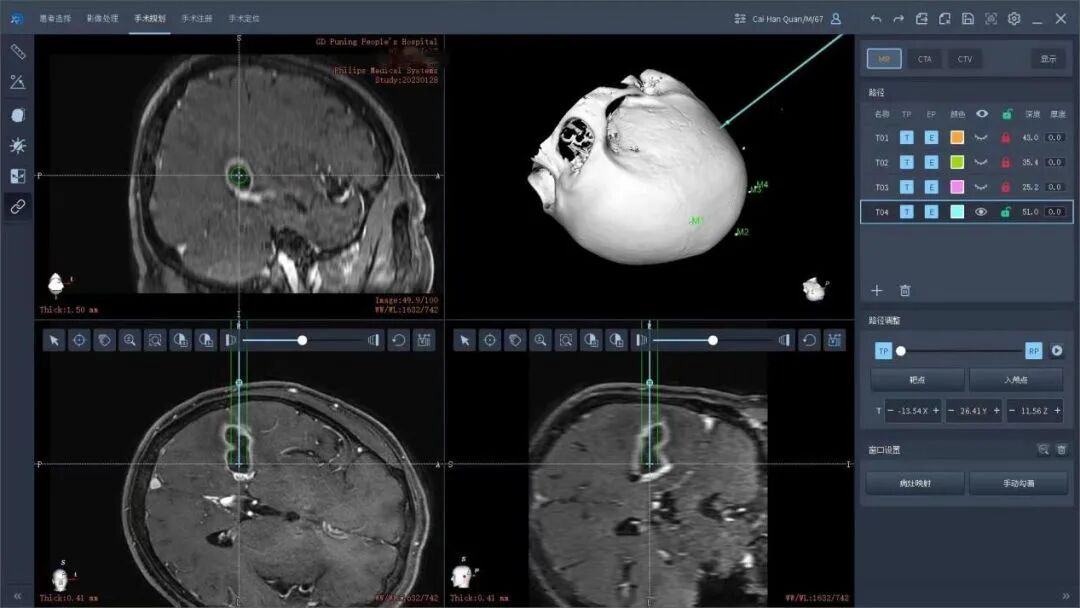

术前,谢树浩医师在患者头部贴上特制的标记后陪同前往CT室行头颅CT检查,在机器人手术计划系统上融合了患者的磁共振、CT等影像检查,避开了重要脑回、血管等重要结构,选择最佳的精准穿刺路径。在黄雪钦副院长指导下,王晓东主任医师治疗团队为陈老伯行机器人手术治疗。手术从机器人的注册、消毒、钻孔、置管一气呵成,置入引流管后,引流管内引流出大约6ml乳白色的脓液,明确了不是恶性肿瘤是脑脓肿的诊断,而且做到了精准无误的脓肿引流。术后陈阿伯清醒后拔除气管插管安返病房,复查头颅CT和mr显示脓肿清除满意。后期根据脓肿的细菌学检查进行下一步规范的抗感染治疗。

术前CT和MR多模态影像融合,设计最佳穿刺路径